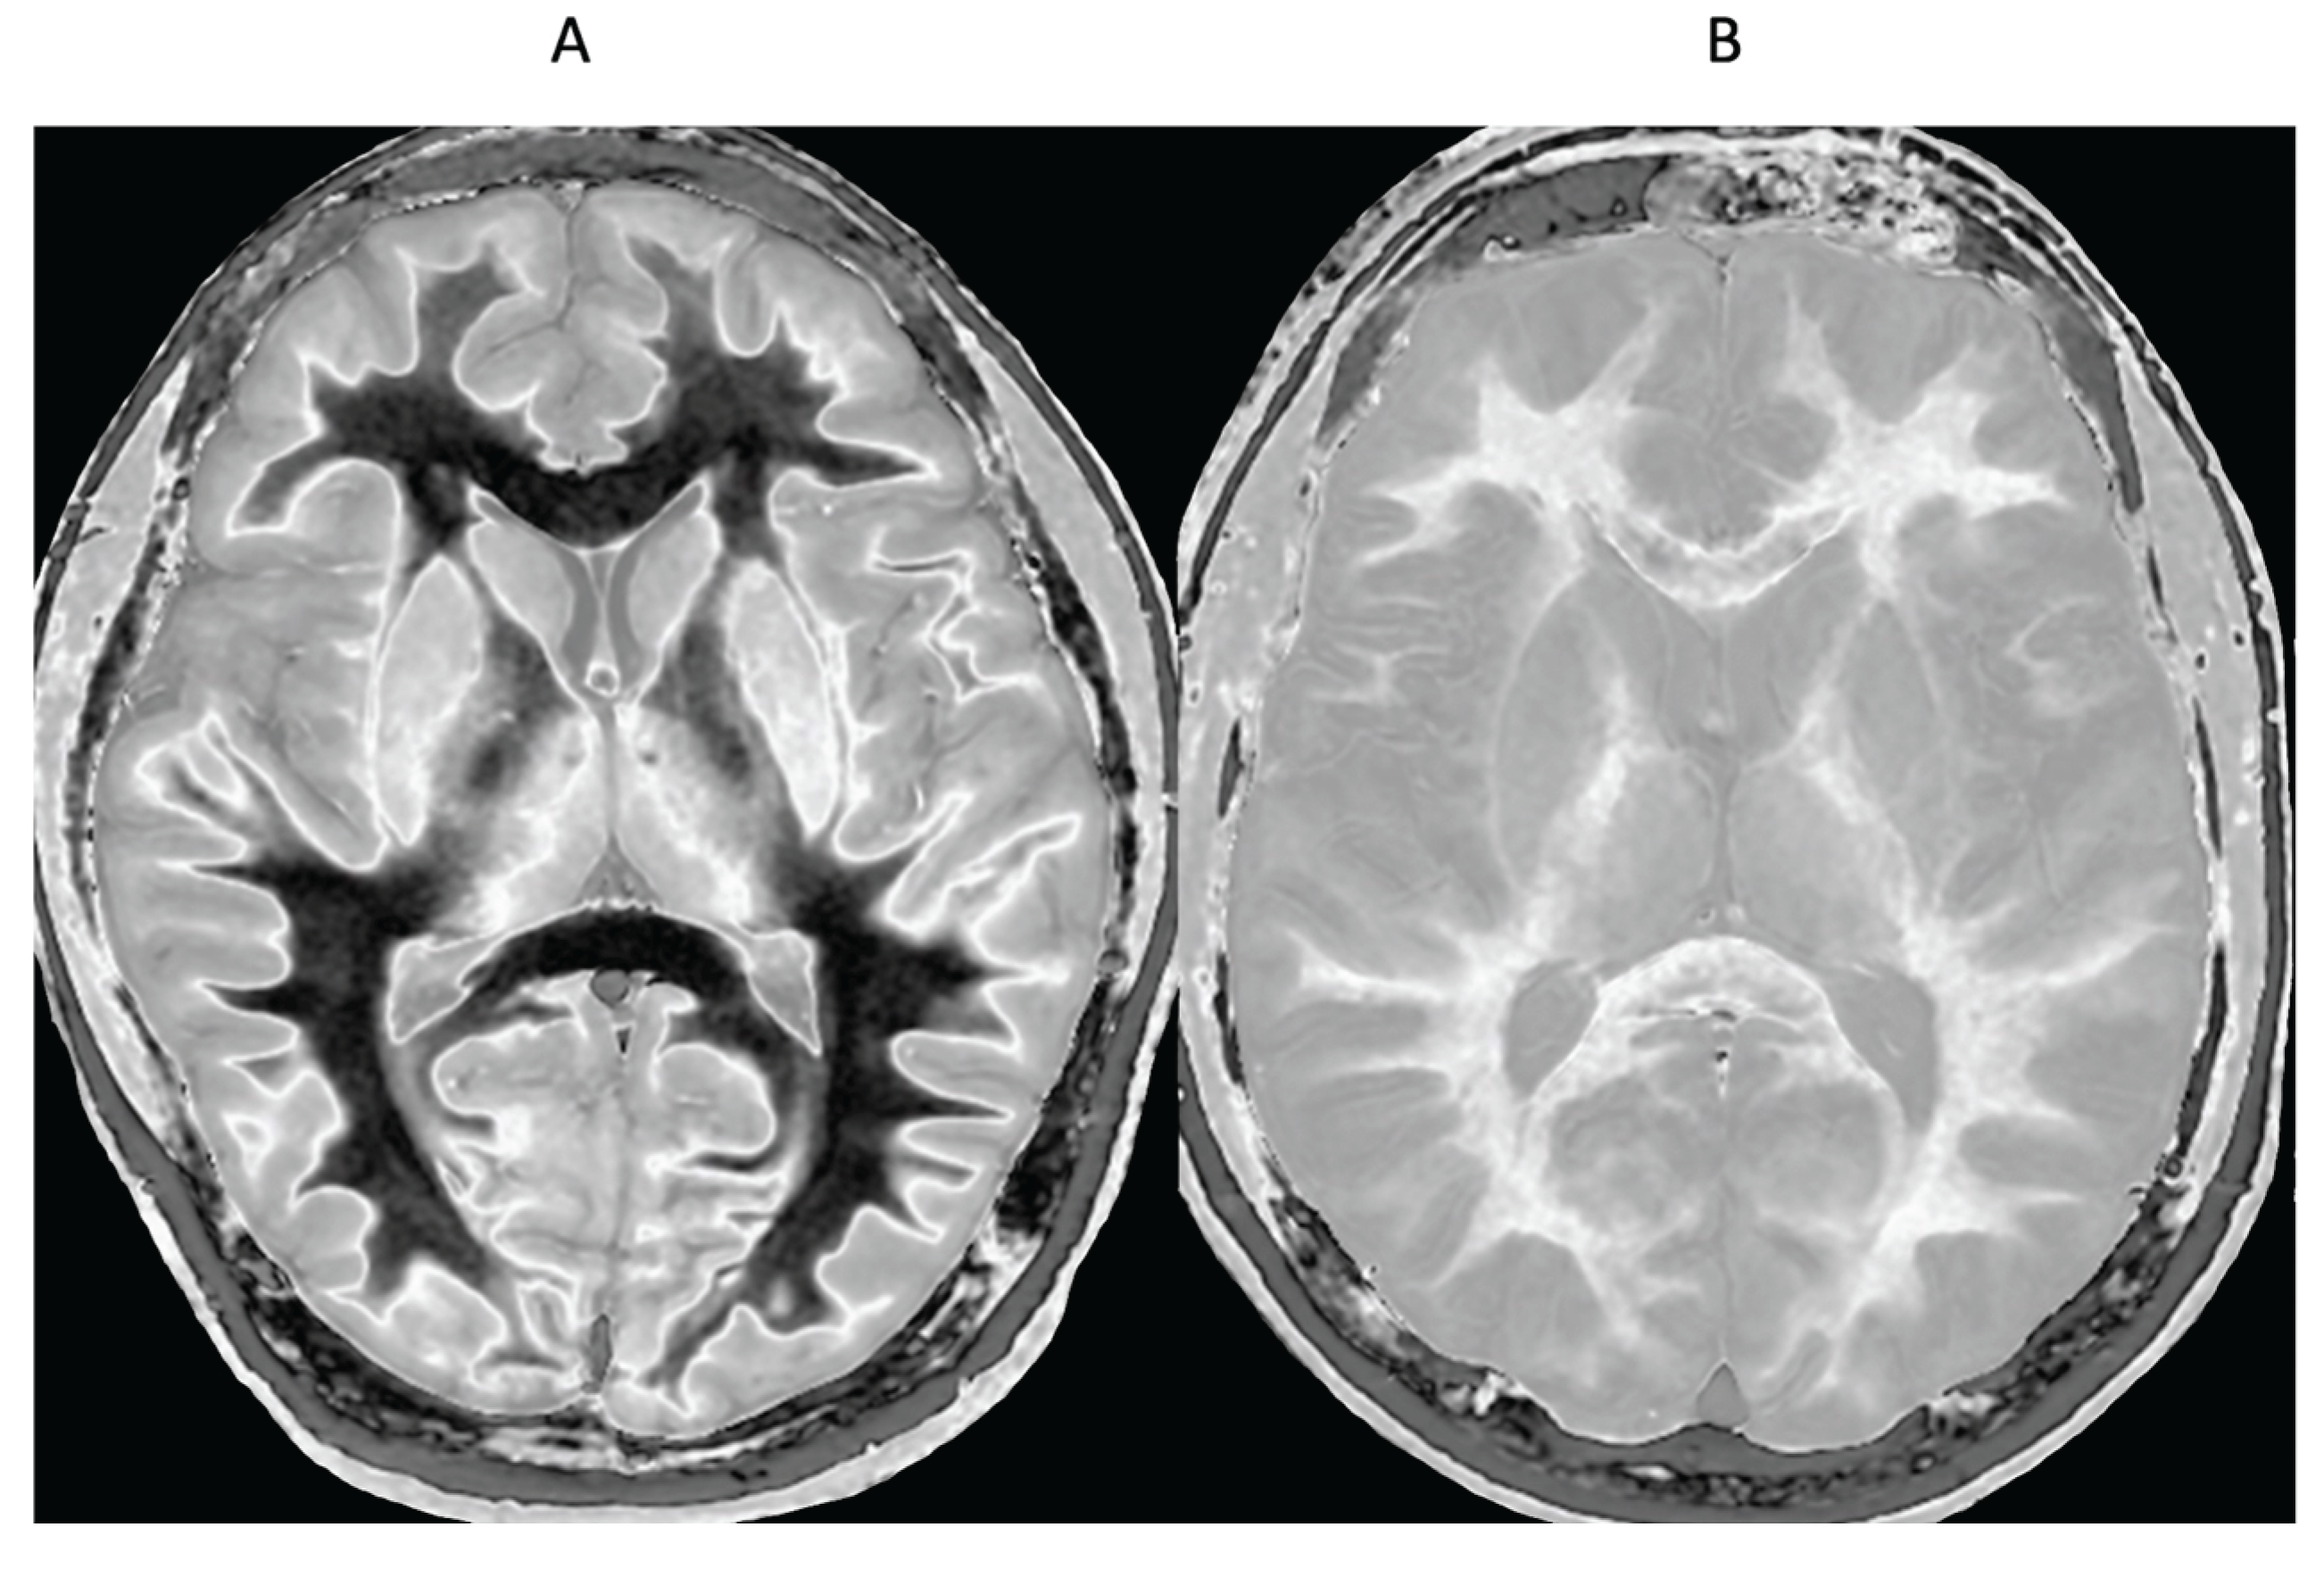

- Methamphetamine Substance Use Disorder

- Delayed Post-Hypoxic Leukoencephalopathy (Grinker’s Myelinopathy)